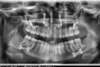

Traitement par gouttières et chirurgie

Début de traitement